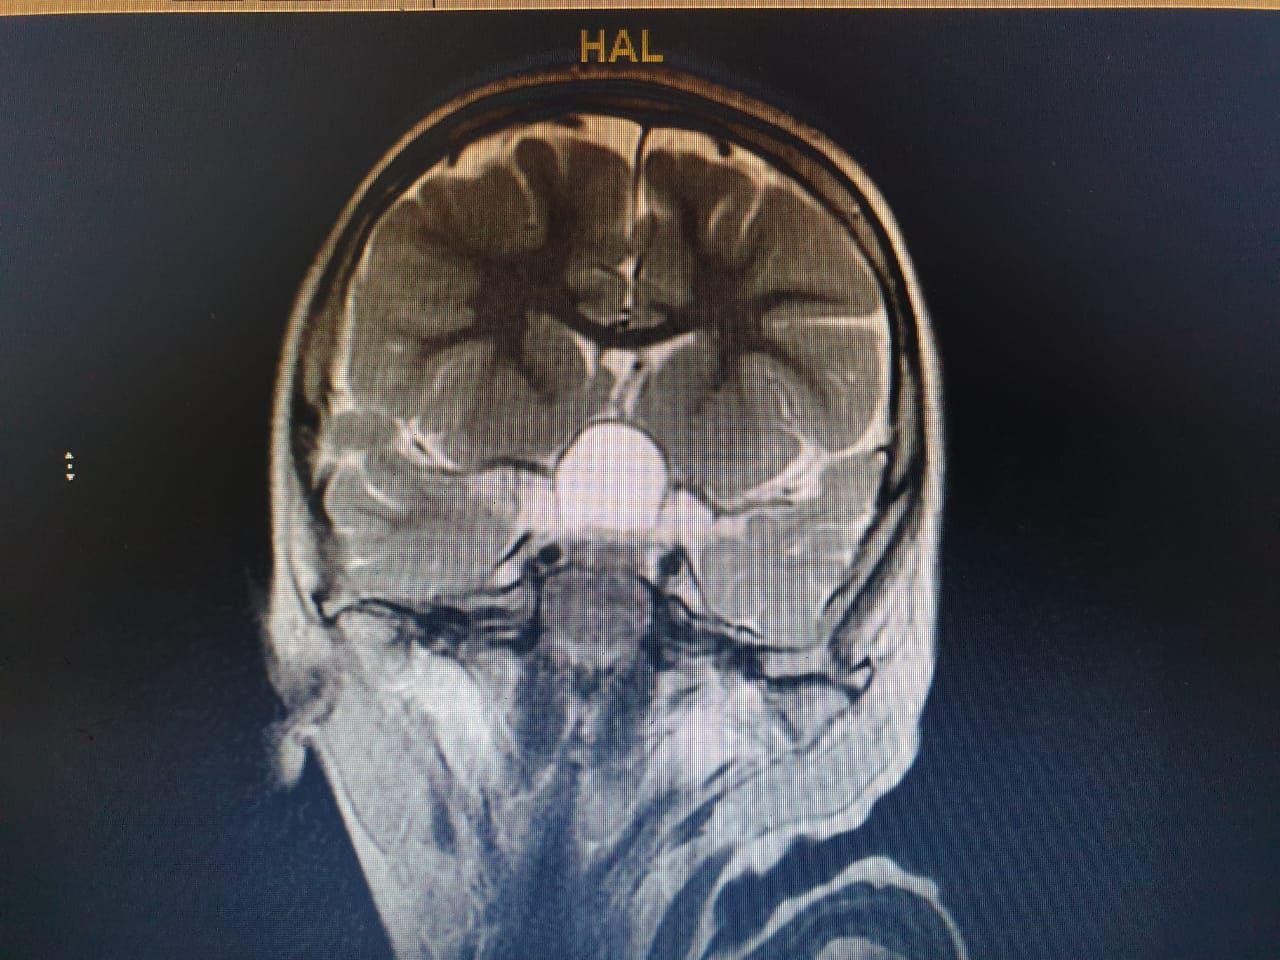

وعلى الفور أجرى الفريق فحوصات متقدمة ، واتضح وجود"ورم" بقاع الجمجمة ، ومتصل بالغدة النخامية.

وأشار المتحدث الرسمي بصحة الطائف سراج الحميدان ,أن الفريق الجراحي للمخ والأعصاب ، تدخل جراحيا بعملية استمرت 7 ساعات لإزالة الورم بالرغم من خطورة الوضع ، وتكللت بالنجاح بفضل الله .